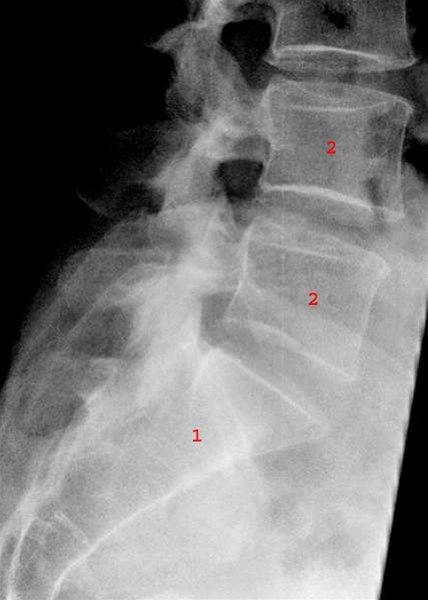

Lumbosacralcolumna, side

Normalt sidebilde av sacrum (1) og de lumbale virvler L4 og L5 (2).